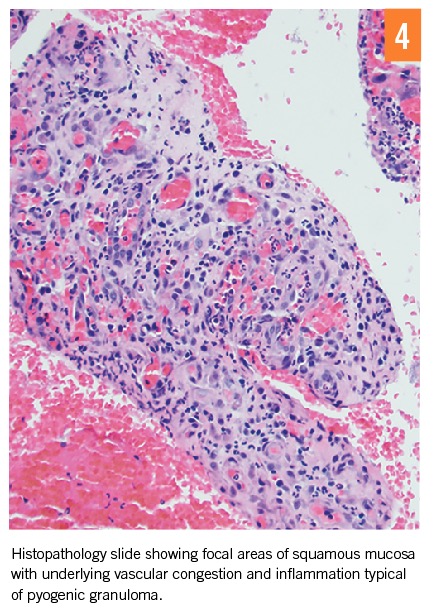

Histopathology of canalicular expression and concretions is the most commonly used diagnostic test.1 Histopathologic findings consistent with pyogenic granuloma have been reported (Figures 3 and 4).1 It is still common for clinicians to diagnose based on histopathology alone.1